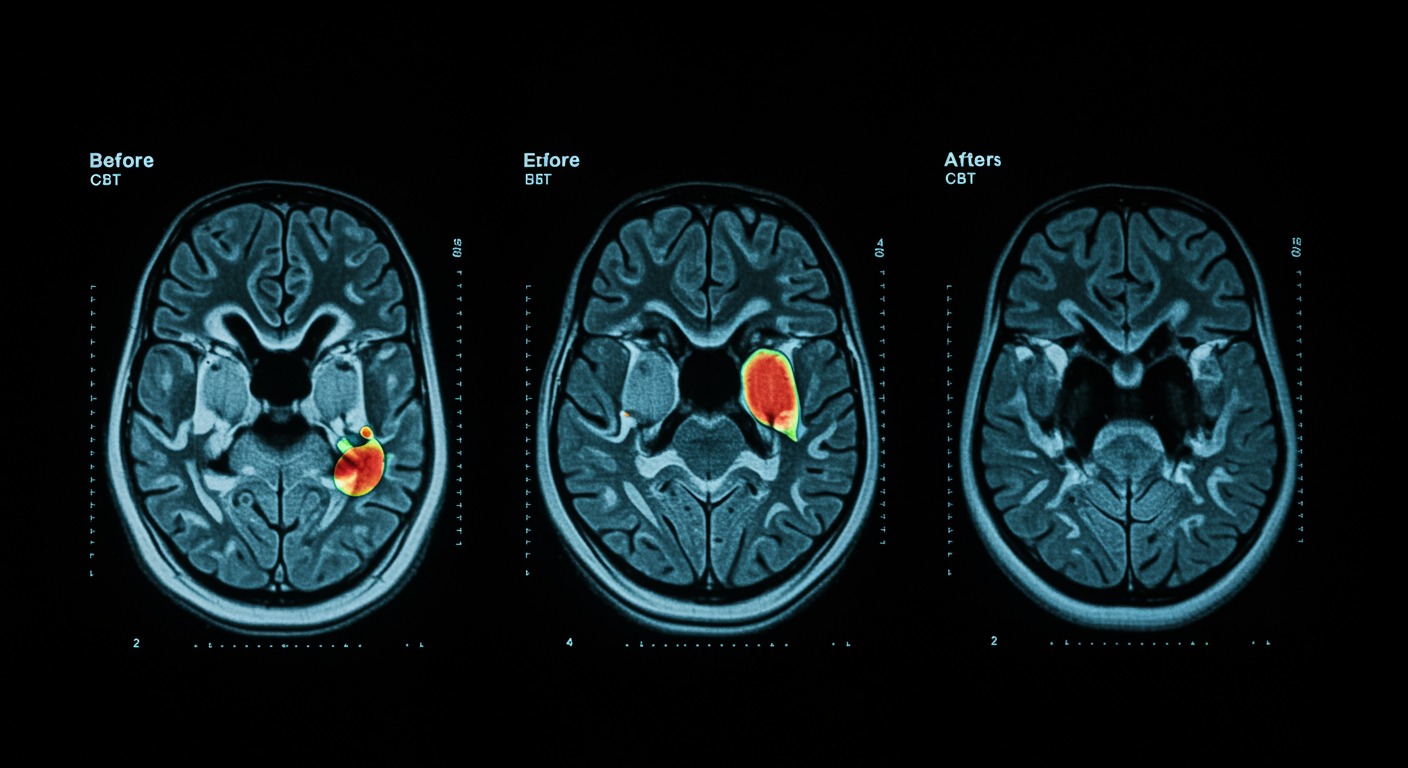

How Different CBT Components Target Specific Brain Mechanisms